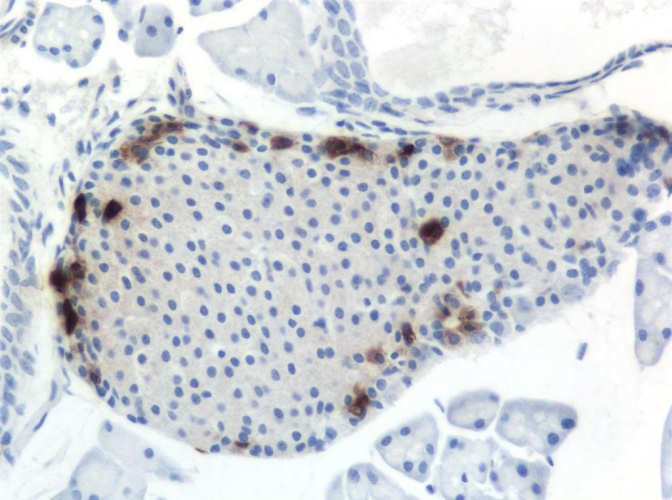

Immunohistochemistry on mouse pancreas for pancreatic polypeptide

Eiland van Langerhans / Islet of Langerhans PP-selle / PP cells